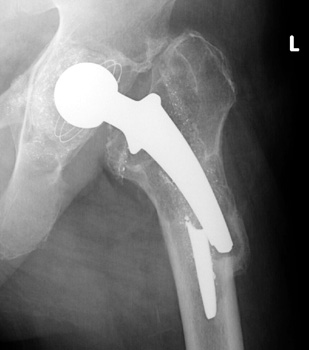

HARDWARE FAILURE

• Hardware fracture / breakage

• Polyethylene wear

• Polyethylene dislocation

Broken femoral stem with remodeling of the lateral femoral cortex.